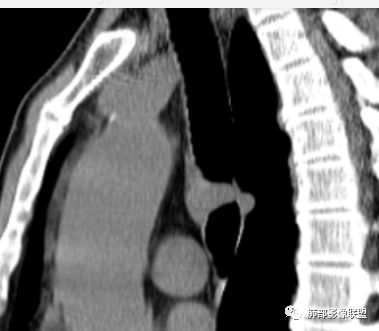

南边分析:针对本例,病灶跨气管壁内外生长,常规跨内外的有:恶性肿瘤为主,其次就是神经源性、平滑肌瘤;常规的思维:跨内外就要看结构的变化气管的优势在于软骨相对密度高,而且成C型

我们如何分析这个病例?冠状位:软骨密度稍高;病灶区软骨部分区域不连续,外围连续,提示病灶推移为主,不是破坏为主;如果破坏,应该这些软骨显示不清,移位不明显

病灶从软骨见推移开,跨内外,因此定在良性。恶性是侵犯,破坏为主,如果破坏,应该这些软骨显示不清,移位不明显,不是推移为主这例病变定在良性,我们就要考虑:1、软骨之间的平滑肌来源;2、神经源性

南边:

南边:高密度软骨在这两点上停了

南边:挤过去了,说明是从软骨间过去的

尘缘:@Shelia,部分是向前推,部分是向后推的。这个地方应该还有向后推的;肿物是从向前推与向后推这个间隙跨软骨的。

南边:需要用连续的窄窗观察。